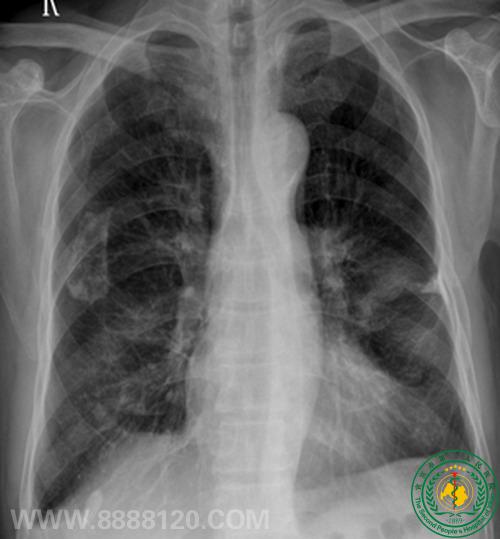

病例3 65  胸痛,余无异常。

DR 示右上肺炎症,CT示右上肺磨玻璃密度结节,考虑多为肺Ca。肺穿刺少许组织送病检:结果为肺泡细胞癌。